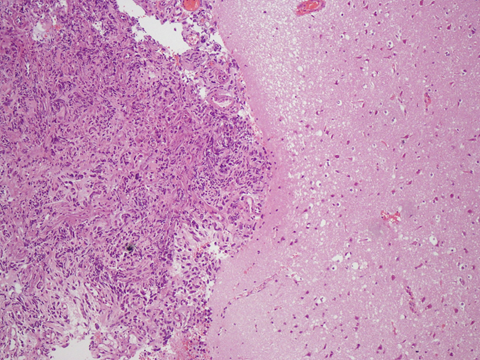

圖1. 惡性腦瘤擴散程度迅速又難以根除,且手術後容易復發。